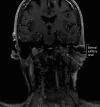

Case report: An 83-year-old woman presented with worsening episodes of dizziness of a few months duration. She also complained of tinnitus and hearing loss, more severe on the left side. Examination revealed a red bulging left-sided tympanic membrane, conductive hearing loss, and a bruit at the base of the skull. Dix-Hallpike test was negative. CT head and MRI brain revealed findings consistent with a large left-sided jugulotympanic paraganglioma, which was found to be hormonally inactive on laboratory tests. The patient underwent treatment with radiotherapy, which resulted in partial improvement of symptoms.

Conclusions: Jugulotympanic paraganglioma may manifest in the elderly with the chief complaint of intermittent vertigo, as in our case. A red bulging mass on otoscopy raises the suspicion, necessitating further investigations, including CT and MRI.